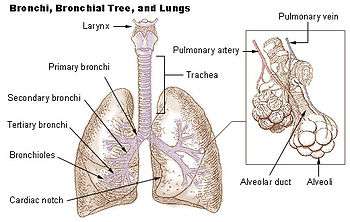

The bronchioles or bronchioli are the passageways by which air passes through the nose or mouth to the alveoli (air sacs) of the lungs, in which branches no longer contain cartilage or glands in their submucosa. They are branches of the bronchi, and are part of the conducting zone of the respiratory system. The bronchioles divide further into smaller terminal bronchioles which are still in the conducting zone and these then divide into the smaller respiratory bronchioles which mark the beginning of the respiratory region.

Bronchioles

The primary bronchi, in each lung, which are the left and right bronchus, give rise to secondary bronchi. These in turn give rise to tertiary bronchi (tertiary meaning third). The tertiary bronchi subdivide into the bronchioles. They are histologically distinct from the tertiary bronchi in that their walls do not have hyaline cartilage and they have club cells in their epithelial lining. The epithelium starts as a simple ciliated columnar epithelium and changes to simple ciliated cuboidal epithelium as the bronchioles decreases in size. The diameter of the bronchioles is often said to be less than 1 mm, though this value can actually range from 5 mm to 0.3 mm. As stated, these bronchioles do not have hyaline cartilage to maintain their patency. Instead, they rely on elastic fibers attached to the surrounding lung tissue for support. The inner lining (lamina propria) of these bronchioles is thin with no glands present, and is surrounded by a layer of smooth muscle. As the bronchioles get smaller they divide into terminal bronchioles. These bronchioles mark the end of the conducting zone, which covers the first division through the sixteenth division of the respiratory tract. Alveoli only become present when the conducting zone changes to the respiratory zone, from the sixteenth through the twenty-third division of the tract.

- Trachea

- Primary bronchus

- Lobar bronchus

- Segmental bronchus

- Bronchiole

- Alveolar duct

- Alveolus